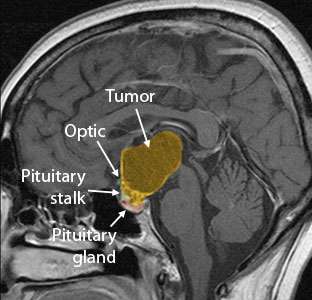

Cranio Sag Preop Before Surgery

Before Surgery

Large craniopharyngioma successfully removed using the Expanded Endonasal Approach.